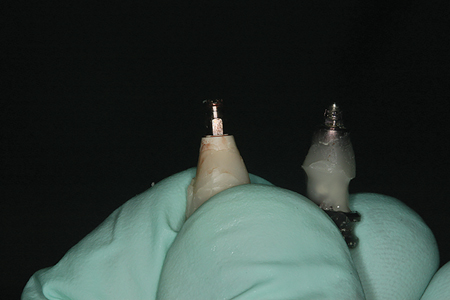

Development of the tissue at the implant site was monitored and modified at two week intervals. An access hole was drilled in the facial aspect of the provisional and it was removed as a screw retained provisional crown at each recall appointment. (Fig. 10) Modifications were made by adding composite to pressure the tissue and the crown was replaced each time. At the six week check appointment, the tissue development and shape of the provisional were approved by the patient and the restoring dentist.3,4 The provisional shape was recorded photographically and with a full arch polyvinyl siloxane impression. Additional digital photographs were made from multiple angles with at least two shade tabs per photograph to assist in shade matching and color mapping (hue, chroma, and value) prior to any dehydration of the teeth.3,4 (Fig. 11)

Fig. 10

The provisional was then removed to visualize the restorative platform of the implant and to evaluate the surrounding tissue contours. (Fig. 12) On the bench, the provisional restoration was seated in an implant lab analog and Clear Bite transparent bite registration material (Den-Mat; Lompoc, CA) was expressed around it to form a matrix to record the subgingival contour of the provisional used to support the soft tissues. The provisional restoration was then removed and an open tray style impression coping was seated in the lab analog within the clear matrix material. Flowable composite was then injected around the impression coping and cured through the clear bite registration material to precisely replicate the emergence profile of the provisional restoration. The modified impression coping was then removed from the lab analog and clear matrix and utilized as a custom impression coping for the master restorative impression. (Figs. 13-16)

Fig. 12